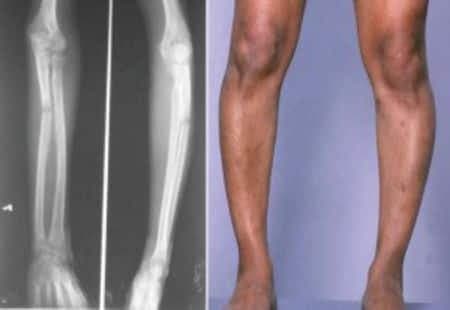

Raşitizm Hastalığı Tedavisi

Raşitizm Nedir, Tanısı, Tedavisi ve Korunma Yolları Raşitizm çocukluk yaş grubunun bir hastalığıdır. Büyümekte olan kemiğin mineralizasyonunun...